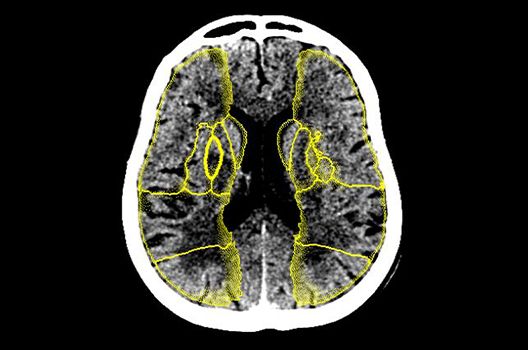

Computertomographie

- Dosis- und Artefaktreduktion

- CT-Bildnachverarbeitung

- Quantitative und automatisierte CT-Bildanalyse

Die Schwerpunkte in der CT-Forschung liegen in der Bildnachverarbeitung, der Dosis- und Artefaktreduktion sowie der quantitativen und automatisierten CT-Bildanalyse.

Die Computertomographie (CT) ist ein Verfahren, bei der mit Hilfe von Röntgenstrahlung Schnittbilder des Körperinneren angefertigt werden. Unser Bestreben ist es hierbei, bei möglichst niedriger Strahlendosis eine bestmögliche Bildqualität zu erzielen. Eine zunehmend große Rolle in der radiologischen Forschung spielen zudem die Automatisierung in der Bildanalyse und die computergestützte Auswertung großer Datenmengen, wie sie bei einer CT-Untersuchung anfallen. Wir arbeiten in enger Kooperation mit den Geräteherstellern zusammen und sind daher maßgeblich an der Entwicklung und Erprobung neuer Techniken beteiligt.